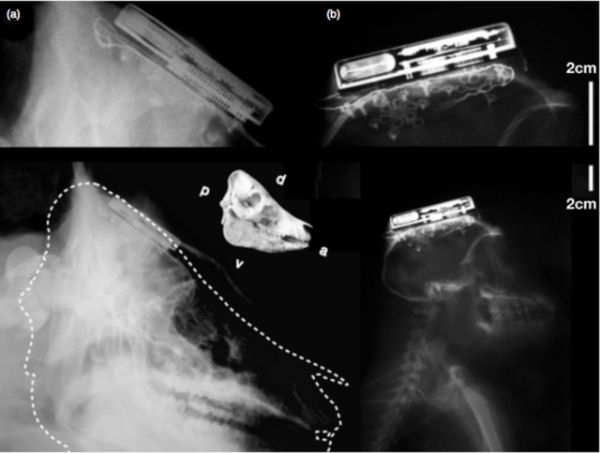

據(jù)外媒報(bào)道,近日,來自布朗大學(xué)的研究人員研發(fā)出了全球首個(gè)通過無線方式連接的腦機(jī)接口。雖然早前也曾經(jīng)出現(xiàn)過多種腦機(jī)接口,但它們?nèi)紵o法通過無線連接,所以常常導(dǎo)致穿戴者的行動(dòng)受限。而現(xiàn)在由布朗大學(xué)研發(fā)的腦機(jī)接口將打破這一局限。

據(jù)介紹,這個(gè)無線腦機(jī)接口個(gè)頭只有一個(gè)火柴盒那么大,它可以放在穿戴者的頭骨進(jìn)行檢測。它將可以將檢測到的數(shù)據(jù)傳輸給在1米開外的電腦。而安放在其中的200mAh鋰離子電池可以讓這個(gè)設(shè)備續(xù)航7個(gè)小時(shí)。